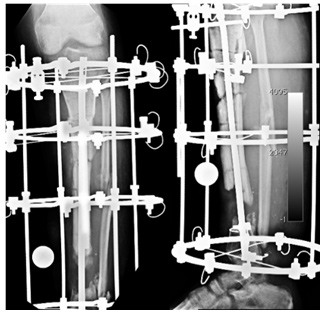

| X-rays at Presentation | ||

| The x-rays showed nonunion at both the upper and lower fracture sites. The lower fracture site showed infection and dead bone. The fixator was not holding the bone fragments in good alignment and the wires were all loose and some of them were infected. | ||

| Bone Transport | ||

| The Ilizarov fixator is applied while the intra-medullary nail is still inside. An osteotomy was done in the proximal aspect for the purpose of bone transport. | ||